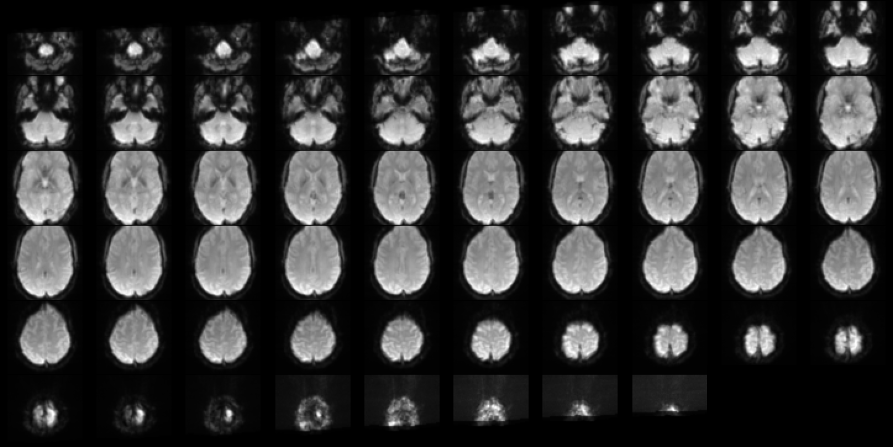

3.8 3D CNN

Refer to caption

Figure 2: A single subject aggregated over the 4thsuperscript4𝑡4^{th} axis

We first started by aggregating data over the 4th axis by their maximum values and minimum values for all the subjects. So we reduced the data size by many folds and captured the data in a 3D space. Now we had a lot of techniques that could be applied to 3D data. A lot of work has been performed in the domain of CT scans. So we adopted a 3D convolutional neural network which was commonly used to classify lung images with pneumonia. We performed minimal argumentation by rotating the 3D image with some angle. The random angle was selected from (-20, -10, -5, 5, 10, 20) every time it was augmented.